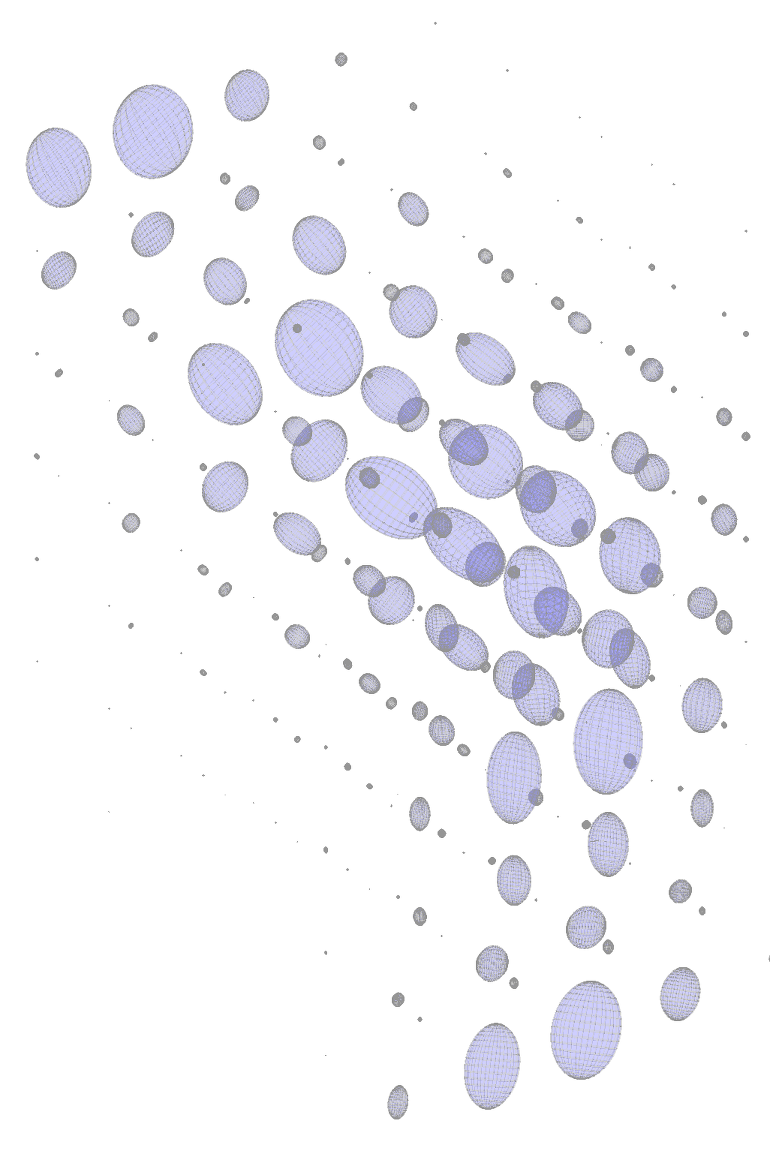

The idea is to convolve finite impulse response SLoGS with the discrete vascular image in a scale- and rotation-invariant framework, to obtain simultaneously the connected vesselness maps and the associated tensor field. For simplicity, the filtering steps will be presented for a generic scale . Scale-invariance is achieved by keeping the size of the small compact-support SLoGS fixed, while the size of the vascular image varies accordingly with the multi-resolution pyramid. Also, different will produce SLoGS kernels with different spatial band-pass frequencies. is down-sampled at the arbitrary scale as proposed in [7] to obtain . An early saliency map of tubular structures is then determined as

is derived from the discretized tubular kernel (fig. 1), whereas is defined as a group of orthonormal basis in , using an icosphere at arbitrary subdivision level to determine the orientation sampling in 3D. is meant to provide an initial, coarse, although highly-sensitive set of saliency features in : the vessel spatial locations and orientations. The identification of such features has two advantages; firstly it restricts the problem of the rotation-invariant filtering to an optimal complexity in 3D avoiding unnecessary convolutions; secondly it allows to use a locally selective overlap-add (OLA) [15] for the analysis/synthesis filtering. In detail, vessel spatial locations are mapped as voxel seeds , and the associated set of orientations forms a group of orthonormal basis in . We define as

The scalar vesselness responses of both HCP and PC images are determined using the state-of-the-art Frangi filter (FFR) [8], and Optimally Oriented Flux (OOF) [12]. Also, the connected vesselness map (CVM) and the associated tensor field (TF) are synthesized for the same dataset using VTrails. The connectedness of the considered scalar maps is qualitatively assessed and the TF is inspected as proof of concept in section 3.1.

Fig. 3 shows the connectedness of vessels recovered from state-of-the-art vascular enhancers and curvilinear ridge detectors FFR and OOF together with the proposed CVM for the synthetic HCP and the real PC images.

On the synthetic phantom, FFR shows a fragmented and rough vesselness response in correspondence of irregularly shaped sections of the structure. Also, the response at the bifurcation is not smoothly connected with the branches (triangular loop). Conversely, OOF recovers the phantom connectedness at the branch-point, and the vesselness response is consistent along the tortuous curvilinear section, however ghosting artifacts are observed as the shape of the phantom becomes irregular (C-like) or differs from a cylindrical tube. Also, close convoluted structures, which change scale rapidly in the HCP, produce inconsistent responses of OOF (fig. 3). CVM shows here a strongly connected vesselness response in correspondence of both regular and irregular tubular sections, with local maxima at structures’ mid-line. The connectedness of the structures is emphasized regardless the complexity of the shape, and it resolves spatially the tortuous curvilinear ‘kissing vessels’ without additional ghosting artifacts, despite the smooth profile.

Similar results are observed on the PC dataset: FFR has a poor connected response in the noisy and low-resolution image. Vessels are overall enhanced, however thin and fragmented structures remain disconnected. Overall, the vesselness response is not uniform within the noisy structures, where maximal values are often off-centred. A more consistent response is obtained from OOF, where the connectedness of vessels is improved. Maximal response is observed at the mid-line of vessels, however, noise rejection is poor. CVM strongly enhances here the vessel connectivity. The fragmented vessels of PC have a continuous and smooth response in CVM with higher values and a more defined profile. Large vessels shows solid connected regions with local maxima at mid-line as in OOF. Conversely from OOF, CVM shows improved noise rejection in the background.

The respective tensor fields (TF) synthesized on both HCP and PC show consistent features. The TF’s characteristics are in line with the connectedness of CVM: enhanced and connected vessels are associated with high anisotropy, whereas background areas show a predominant isotropic component.